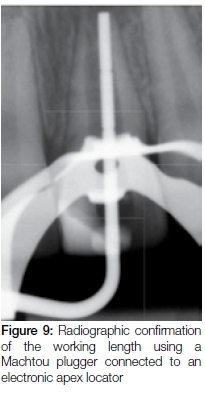

A 17-year-old male presented in private practice with a history of previous dental trauma to his maxillary right central incisor about nine years previously. A pre-operative periapical radiograph revealed incomplete root closure associated with a wide-open apex and a large periapical lesion (Figure 8). After placement of a rubber dam an access cavity was prepared. Length determination was accomplished using Machtou pluggers (Denstply Sirona) and an electronic apex locator (Pixie Electronic Apex Locator, Dentsply Sirona). The working length was confirmed radiographically (Figure 9).